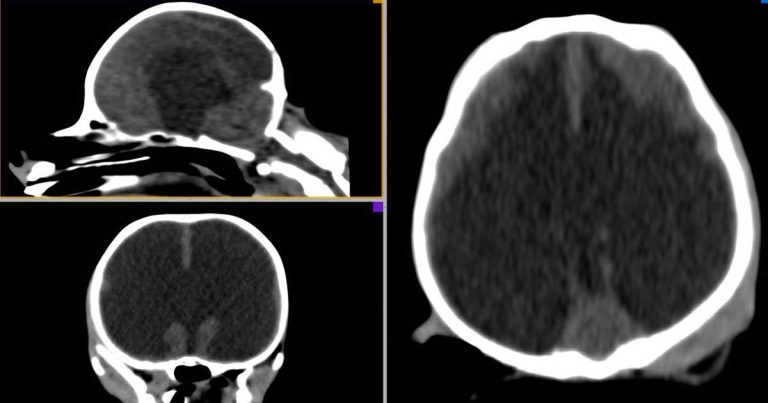

Diagnosis of hydrocephalus is usually made with the help of advanced imaging techniques (MRI and CT; Figures 1 to 3) that provide information about the type of hydrocephalus and the hydrocephalus that requires treatment. Ultrasound may help in some cases (Figure 4).

An MRI examination of the dog’s brain has revealed it has a markedly enlarged ventricular system. Can a diagnosis be made?

When reviewing advanced imaging pictures in dogs with suspected hydrocephalus, it must be remembered that ventriculomegaly and hydrocephalus are not synonymous; not all animals with ventriculomegaly have hydrocephalus. For example, asymmetric and symmetric enlargement of the lateral ventricles can be seen in neurologically normal dogs.

To correctly diagnose that the dog has clinically significant hydrocephalus, the signalment and clinical signs need combining to some specific features on imaging that can help support the diagnosis, such as: